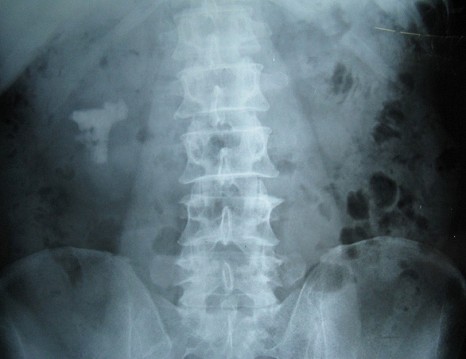

1 术前KUB平片可以清晰地看到右肾复杂性铸型结石